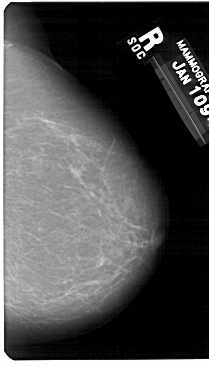

A_1271_1.LEFT_MLO

LEFT_MLO LINES 5491 PIXELS_PER_LINE 3331 BITS_PER_PIXEL 12 RESOLUTION 43.5 OVERLAY